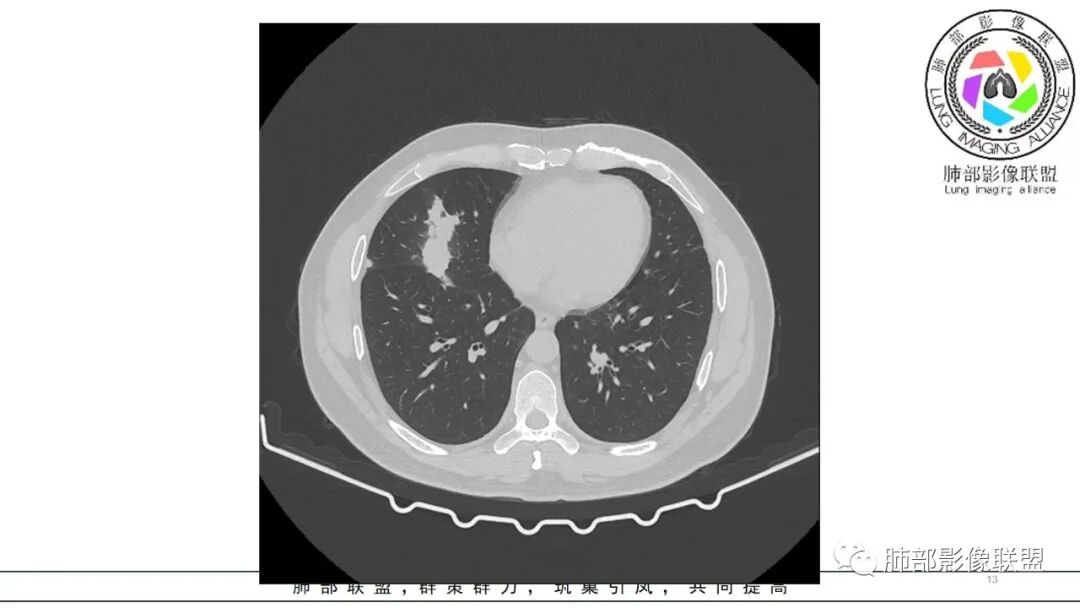

中年男性,咳嗽咳痰低热三天。右肺中叶、下叶条片状高密度影,局部边缘有晕,可见卫星灶。双肺另见多发小结节。考虑炎性肉芽肿,PC,鉴别GPA

双肺多发实性小结节,边清,多位于胸膜下。右肺中叶不规则实变影,沿支气管血管束走行,似有跨叶。

分布有点怪异,多灶,胸膜下,外周小结节,中叶病灶跨叶,似乎与支气管垂直,不是平行关系,蠕虫样,周围渗出,内部坏死,血道来源?肿瘤不能解释,感染性肉芽肿炎不像,中耳炎病史,痰中血丝,GPA?寄生虫?嗜酸如何?查anca、肾功、寄生虫抗体

双肺胸膜下多发结节,部分结节内可见空洞影。右肺中叶斑片影(类似指套征),并可见右肺中叶支气管壁增厚。看到病史的时候,看到鼻窦炎,中耳炎。想到如果与鼻窦炎相关,1.有GPA,但是GPA,典型是鼻,肺和肾的病变,有鼻窦炎,软骨受累,眼睛受累红肿等。晨读没有提到肾方面损害。另外,晨读的结节更多表现为血播,与支气管血管束关系不大。如果是GPA应该主要是与血管相关,与支气管血管束密切相关。2.和鼻窦炎有关的真菌感染,曲霉?但是肺内病变难以一元,右肺中叶与气道相关,双肺多发结节与血道相关。不是说一般气血难以兼容。还有就是如果是曲霉的指套,密度偏低了。3.按两肺多发结节方向考虑,隐球菌需要鉴别。总之,晨读隐球菌>GPA>真菌曲霉

男,47岁,咳嗽咳痰发热三天,既往中耳炎病史。CT示双肺多发随机分布小结节,多位于胸膜下,部分伴小空洞,右肺中页不规则实变影,沿支气管血管束走行。实验室检查血沉,CRP增高。综合考虑为感染性病变,隐球可能,鉴别GPA

双肺多发结节,以胸膜下分布为主,形态相似,边缘较规整,少部分边缘晕征,无分叶毛刺;右肺中下叶多结节融合并实变影,边缘平直、U形征,跨叶。

病灶与支气管血管束无关,定位肺实质来源病变,考虑良性病变,炎性肉芽肿病变:隐球可能。

急性起病,中耳炎病史,右中叶病灶呈蠕虫样,跨叶生长,水平裂牵拉移位,两肺胸膜下多发结节灶,血道来源,病史支持感染性,没有免疫抑制,无咯血不支持曲霉及血管炎,急性病史也不支持TB,右中叶病变呈蠕虫样,有点小细胞癌的征象,但小c转移常见的是肺门和纵隔,本例也不支持,综和考虑支持炎性肉芽肿GPA,鉴别PC

中年男性,咳嗽咳痰低热3天,偶有血痰。有鼻炎、中耳炎病史。右中叶病灶呈指套样,跨右下叶,叶间胸膜牵拉移位。两肺胸膜下多发结节灶,边缘模糊见晕征,部分呈空洞结节。白细胞计数及CRP、血沉稍高。跨叶的指套样病灶有小细胞肺癌的影像特点,两肺多发结节,但近肺门、纵隔无肿大淋巴结,不符合小细胞肺癌的转移特点,考虑非肿瘤病灶。没有典型的多形态、未见树芽征,肺结核可能性小;两肺胸膜下病灶有晕征,存在隐球菌病可能,但右中下叶的主病灶形态在隐球菌病中罕见;有鼻炎病史,肺内病灶存在血管炎可能;患者为银行职员,应该经常接触纸币,有血痰症状,主病灶呈指套样,两肺多发晕征及空洞,存在曲霉菌感染可能。综上考虑肺曲霉菌病可能,鉴别血管炎、PC、TB。